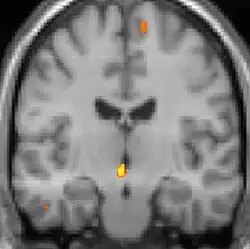

![]() |

| Tomografia PET mostrando áreas ativadas na dor. | ||

| VBM mostrando diferenças estruturais entre cérebros | ||

As reais causas da cefaleia em salvas (CES) ainda são desconhecidas, mas, de acordo com alguns estudos, os padrões das crises, as influências pelo horário do dia e as estações sugerem que o relógio biológico do corpo está envolvido. Nos seres humanos, o relógio biológico está situado no hipotálamo. Durante um ataque, o hipotálamo libera substâncias químicas que podem estimular as células nervosas no cérebro, causando dor e outros sintomas. A hiperatividade nervosa também pode causar um alargamento (vasodilatação) das artérias no lado afetado do cérebro. Uma teoria é que as dores são causadas por um alargamento dos vasos sanguíneos, que pressionam sobre os tecidos nervosos próximos, causando dor.[5] Exames de ressonância magnética sugerem dilatação da artéria oftálmica durante uma crise de cefaleia, enquanto a tomografia por emissão de pósitrons (PET) revela atividade dentro do seio cavernoso. Em alguns casos, existem fatores genéticos também, pois é mais comum entre familiares.[6]